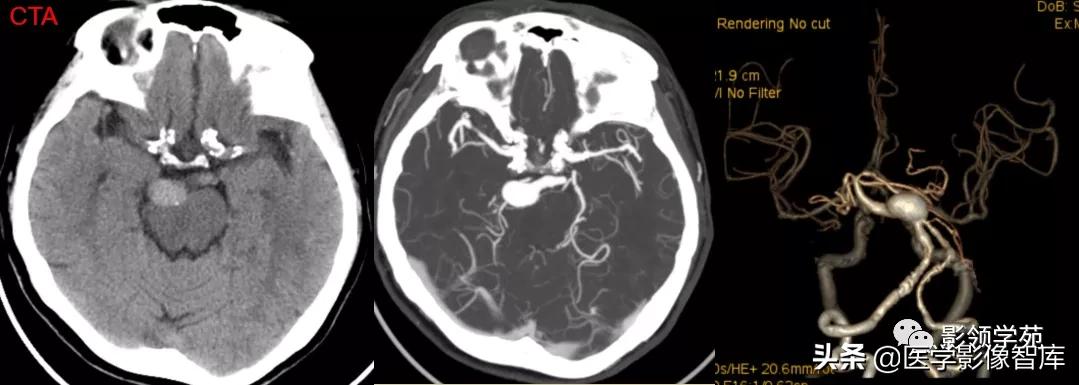

女 61岁 反复头晕3年余

鞍上可见一类圆形均匀稍高密度灶,CT值约47HU,

边界清楚,其内见一小点片状钙化灶;继发鞍上池受压伴变性。

鞍区占位肿块,呈等T1等T2信号,信号均匀,边界清楚。

病灶呈均匀、显著强化(馒头样),以宽基底与前颅窝底相连,

冠状位和矢状位见脑(硬)膜尾征;

肿块突入鞍上池,向上推压视交叉,后缘紧邻垂体柄,与双侧颈内动脉相邻。

(脑膜尾征:增强扫描,肿块邻近的增厚硬脑膜呈窄带状强化,随着远离肿瘤

而逐渐变细。)

颅内动脉走形自然,管壁光滑,未见局灶性异常狭窄或扩大征象。